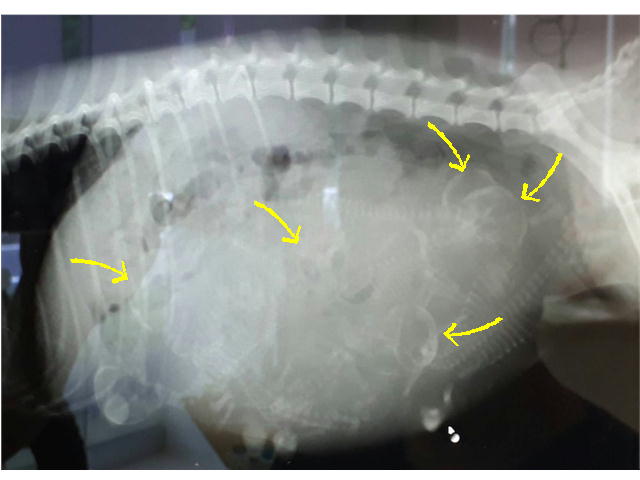

H30.8.11妊娠56日目になりました。 出産予定日が近づいてきましたので、お産室を組立てました。 当犬舎のお産室は、母犬のストレスを少なくするため、母犬が自由に出入りできる仕組みになっています。 また、母犬がお産室を自由に出入りできることで、母犬は日常的に使用しているトイレ(お産室の外のトイレ)で用を済ませることができますので、お産室を清潔な状態で保つことができます(^^)v ※写真と動画は昨年のものです。 |